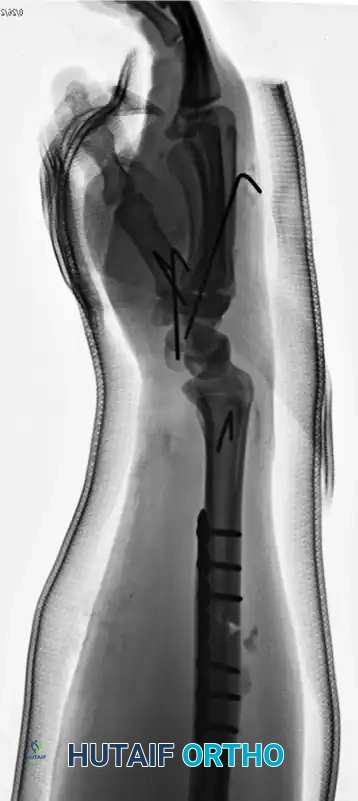

Galeazzi Fracture-Dislocations

A Galeazzi injury involves a fracture of the distal third of the radial shaft coupled with a dislocation or subluxation of the DRUJ. These are highly unstable injuries that mandate operative intervention in adults.

The radius must be anatomically reduced and rigidly fixed, typically utilizing a dynamic compression plate (DCP) or a locking compression plate (LCP). Following radial fixation, the DRUJ must be assessed for stability throughout the forearm arc of motion. If the DRUJ remains unstable, it is often pinned in supination using parallel Kirschner wires.